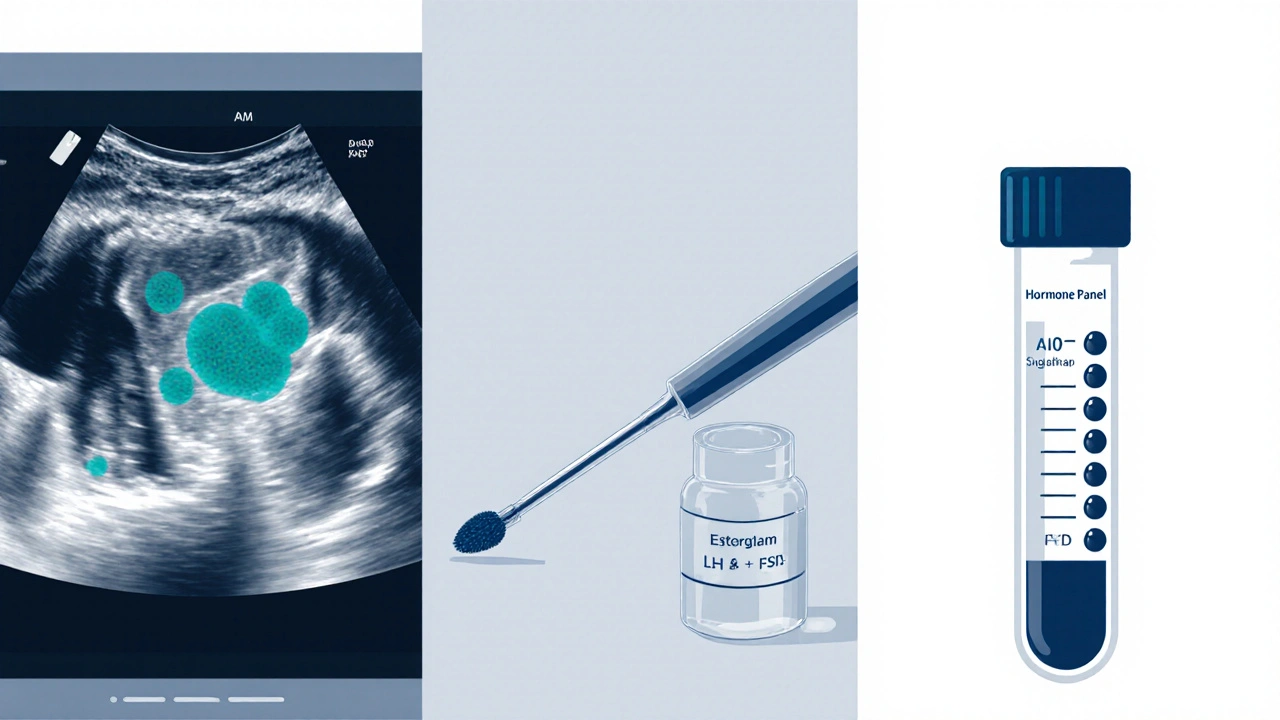

Most appointments include three core elements that directly affect cycle regularity:

- Pap smear - screens for cervical changes that could indirectly affect hormone production.

- Pelvic ultrasound - visualizes ovarian follicles, showing whether they’re developing correctly each cycle.

- Hormone panel - a blood test that quantifies key hormones, flagging imbalances before they cause missed periods.